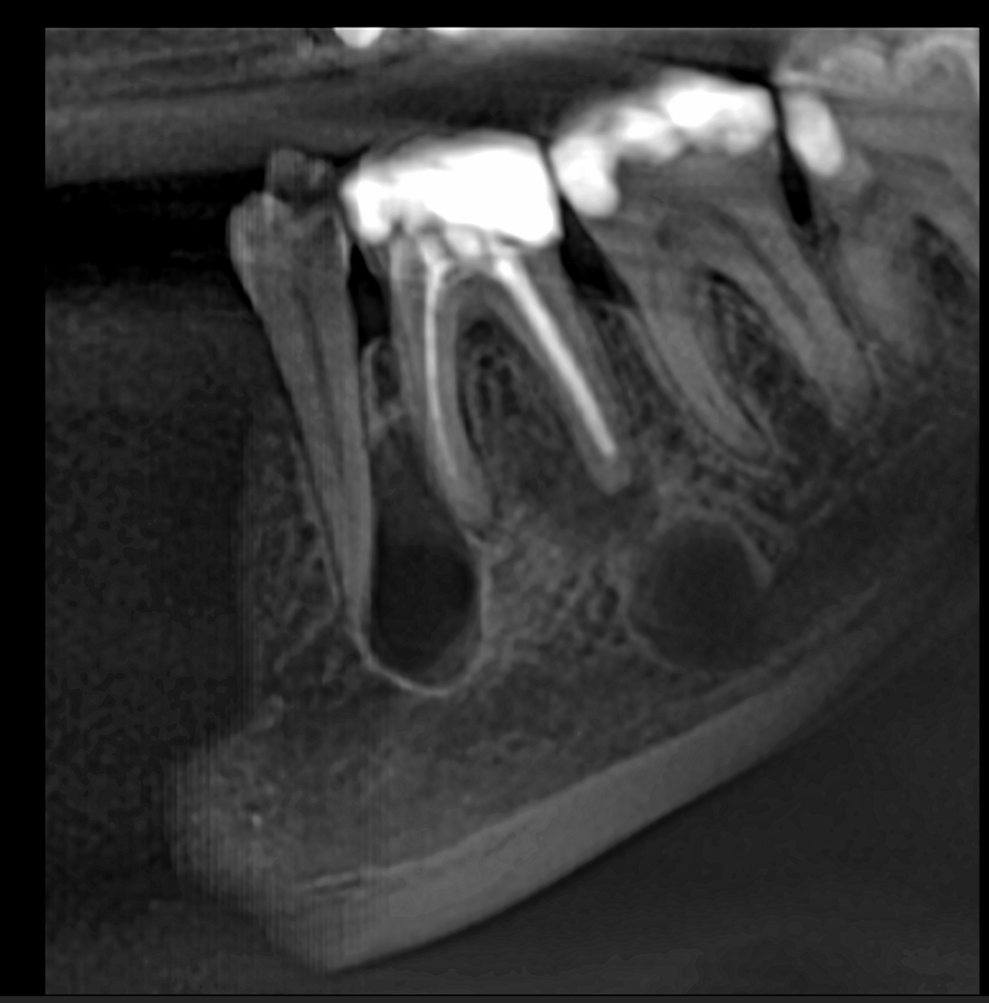

In this first case, the patient, who lived abroad and was unable to travel at the time, had swelling of her right mandible (Fig. 6), had had breast cancer and had been under bisphosphonate treatment for 18 months. She sent a panoramic radiograph (Fig. 7), and this showed a minor apical infection of the mandibular right first molar, which had undergone endodontic treatment. A CBCT scan was then taken, and from examining her scan, we could clearly see an area of bone densification (Fig. 8). This should be a red flag because this indicates the start of bone necrosis.

Fig. 8: Axial view of the CBCT scan showing a small apical infection of the mandibular right first molar, surrounded by an area of dense ossification extending over a large part of her mandible.